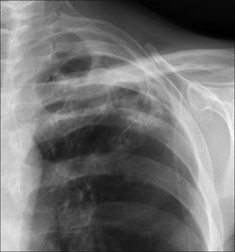

image

Figure 30.7 Haemoptysis due to a bronchial carcinoma. A central tumour at the right hilum. In most instances of haemoptysis resulting from a lung carcinoma the bleeding is mild and caused by the tumour eroding small vessels.